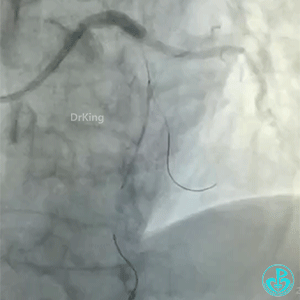

导丝怎么扩真怪!急性心梗前降支导丝通过顺利,球囊扩张后导丝移位很多!不在原来的血管腔!_https://www.jmylbn.com_新闻资讯_第4张

前降支也后扩了。

微导管造影,后面还是放了支架。